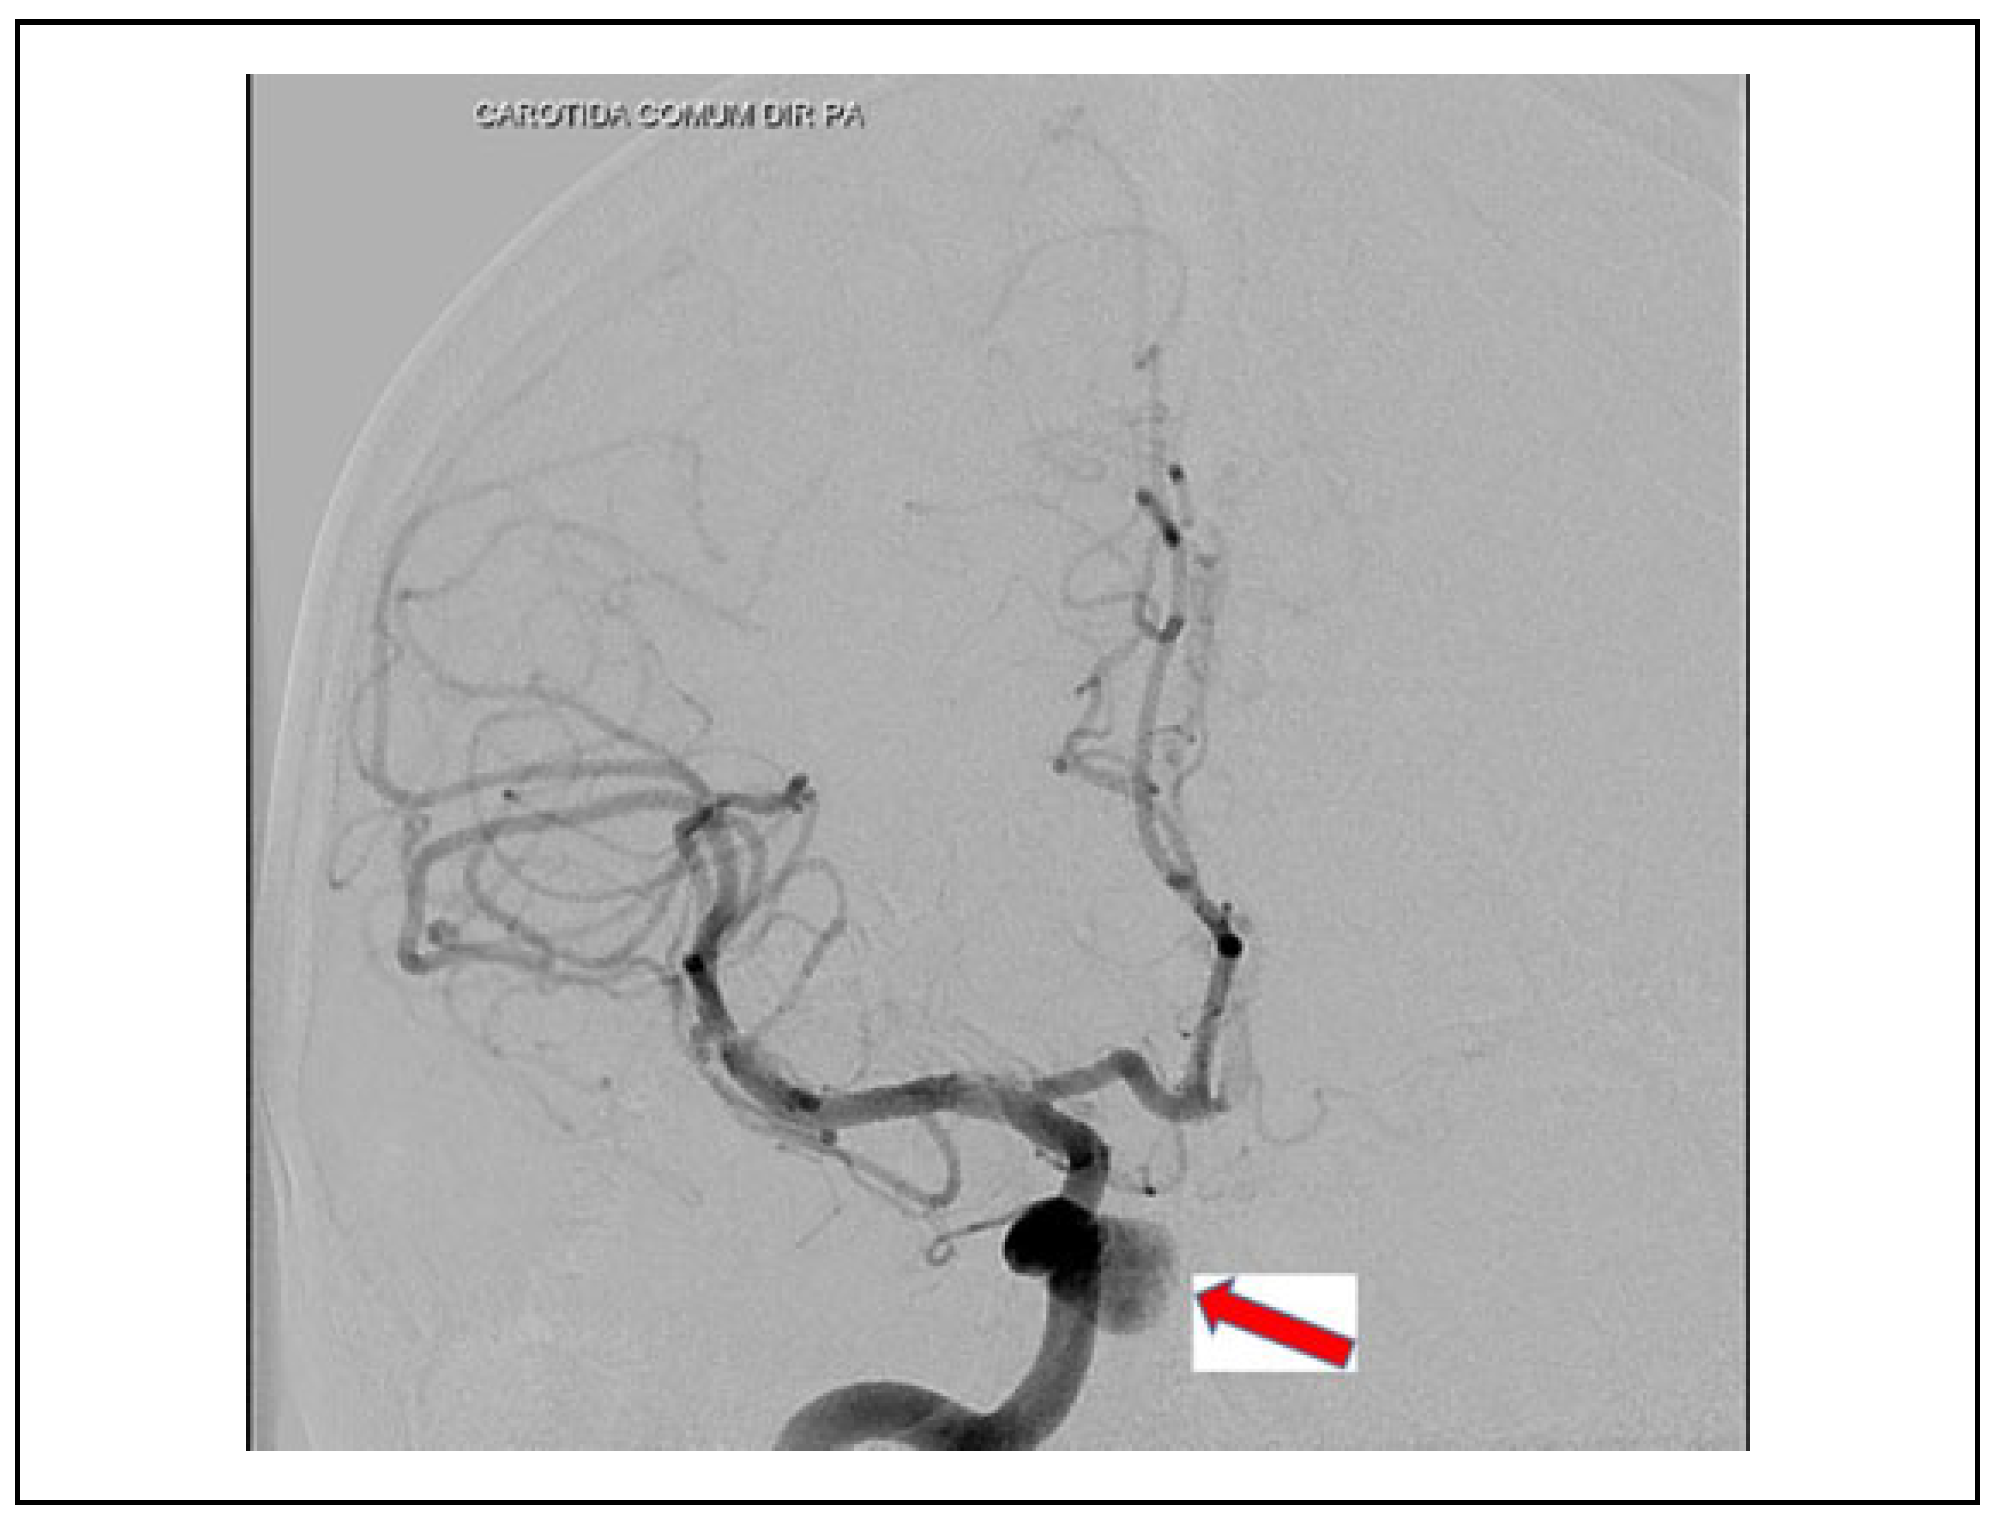

Case 1

Case 2

Case 3